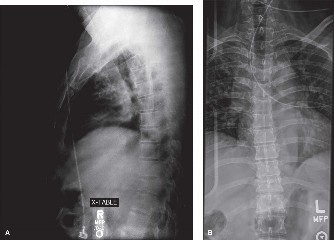

When surgical intervention becomes unavoidable, meticulous pre-operative planning is the cornerstone of a successful outcome. Advanced imaging is non-negotiable. An MRI with and without gadolinium contrast is the gold standard for defining the extent of the epidural abscess, the degree of neural compression, and the involvement of adjacent paraspinal musculature (e.g., psoas abscess). T1-weighted images typically show hypointense signals in the infected marrow, while T2-weighted and STIR sequences reveal hyperintense fluid and edema in the disc space and vertebral bodies. Gadolinium enhancement highlights the vascularized inflammatory phlegmon and the capsule of any abscesses.

In addition to MRI, a fine-cut computed tomography (CT) scan is essential for evaluating bony destruction. CT allows the surgeon to assess bone stock for pedicle screw purchase and to template the size of the interbody cages required for anterior column reconstruction. Upright standing radiographs (if the patient can tolerate them) or full-length supine films are necessary to evaluate global spinal alignment and regional kyphosis.

During the first six weeks, the patient is typically maintained on intravenous antibiotics. A peripherally inserted central catheter (PICC) line is placed prior to discharge. Immobilization is a critical adjunct, particularly for medically managed patients. A rigid thoracolumbosacral orthosis (TLSO) or a custom-molded rigid lumbar brace is employed whenever the patient is out of bed. It is imperative to note that a simple elastic lumbar corset is entirely inadequate; it provides symptomatic warmth but zero biomechanical restriction. Rigid orthoses restrict gross motion, thereby decreasing micro-motion at the infected segment, alleviating mechanical pain, and facilitating the early stages of bony consolidation.